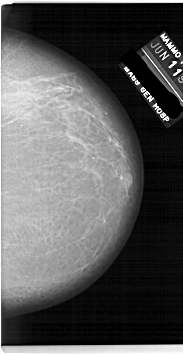

A_1920_1.RIGHT_MLO

RIGHT_CC LINES 6736 PIXELS_PER_LINE 3466 BITS_PER_PIXEL 12 RESOLUTION 43.5 NON_OVERLAY

FILE: A_1920_1.LEFT_CC.OVERLAY

TOTAL_ABNORMALITIES 1

ABNORMALITY 1

LESION_TYPE MASS SHAPE OVAL MARGINS OBSCURED

ASSESSMENT 3

SUBTLETY 4

PATHOLOGY BENIGN

TOTAL_OUTLINES 1

BOUNDARY